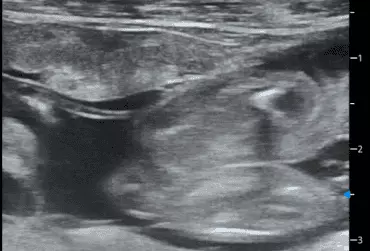

W literaturze opisano niewiele przypadków ciąż bliźniaczych jednokosmówkowych u suk. W trakcie wczesnej diagnostyki ultrasonograficznej ciąży u suki rasy whippet (chart angielski) zobrazowano pęcherz ciążowy, w którym znajdowały się dwa zarodki. Podczas badań kontrol­nych zarodki, a później płody wykazywały prawidłową organogenezę i żywotność. Ich rozwój przebiegał podobnie względem pozostałych ośmiu płodów. W 63. dniu ciąży wykonano zabieg cesarskiego cięcia i wydobyto dwa płody tej samej płci, o bardzo podobnym wyglądzie, z dwóch pęcherzy płodowych przyczepionych do jednego łożyska, oraz pozostałe osiem płodów.

Ryzyko związane z ciążą bliźniaczą jednokosmówkową u ciężarnych suk nadal jest nieznane, istnieją jednak doniesienia o śmierci płodu lub płodów w ciążach jednokosmówkowych u tego gatunku. Badanie ultrasonograficzne w czasie ciąży pozwala na wczesne rozpoznanie ciąży jednokosmówkowej, a monitorowanie żywotności płodów może ograniczyć ryzyko powikłań położniczych i przynieść korzyści zdrowotne zarówno samicy, jak i rodzeństwu z miotu.